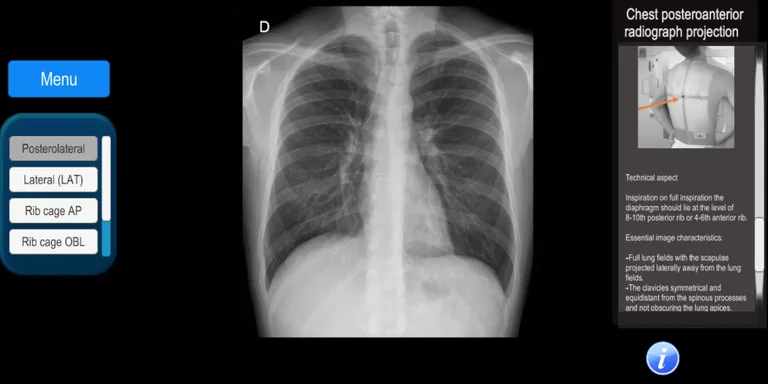

It is an app that allows the user to know the radiological projections that are used daily in a patient care. It covers all areas of the human body with more than 100 digital radiographs: skull, maxillofacial, spine, chest, abdomen, pelvis, upper and lower extremities.

The anatomy of the studied area is described, as well as the technique used for positioning the radiographic projection.